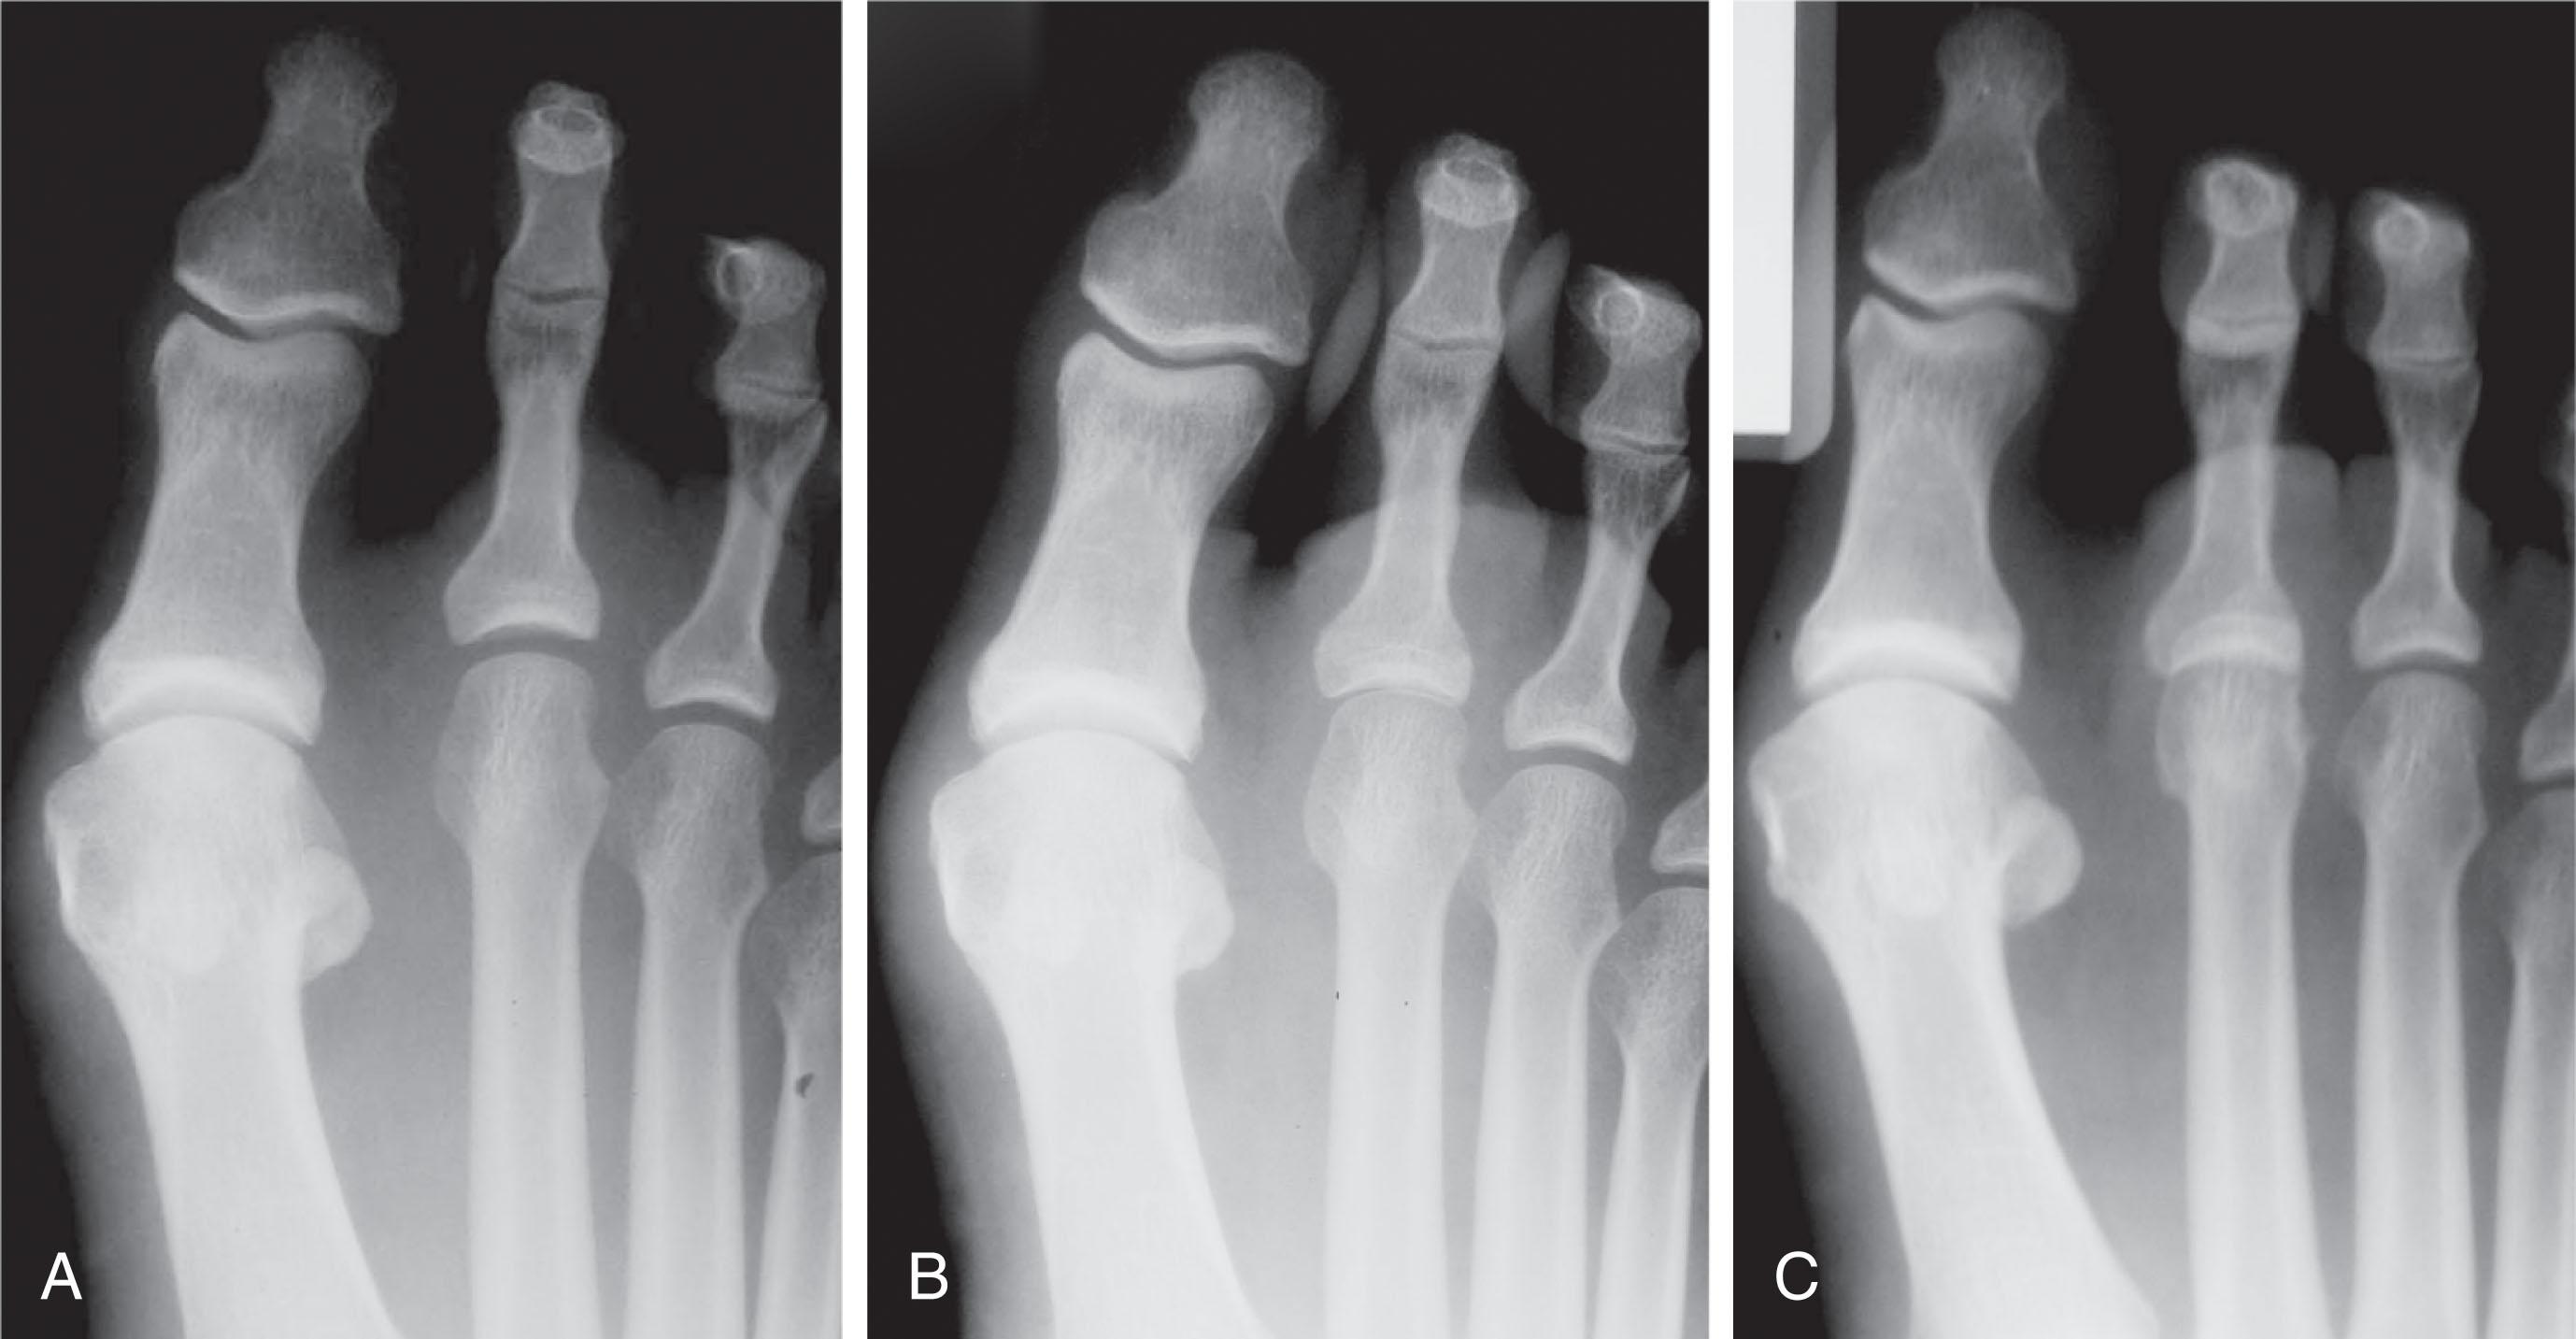

Intramedullary fixation for hammer toe correction has been advocated in an effort to secure permanent fixation without the use of Kirschner wires. Absorbable implants, screw fixation ( Figs. 9-41 and 9-42 ), wire loops, and other permanent intramedullary devices ( Fig. 9-43 ) have all been reported.

Fig. 9-42, Example of screw fixation with hammer toe repair. A , Clinical preoperative photograph and, B , radiograph of hammer toe deformities of second and third toes. C , Postoperative clinical photograph and, D , radiograph after placement of oblique proximal interphalangeal joint screw fixation.